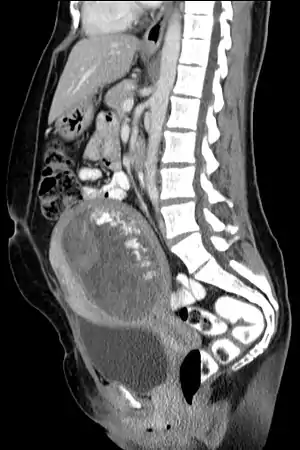

O sangramento no quarto ou quinto mês indica a complicação, e o útero e ovários costumam estar visivelmente maiores que o esperado para esse mês. Os tumores hidatiformes são visíveis numa ecografia ou ultrassom. As análises de sangue e de urina detectam níveis excessivos de gonadotrofina coriônica humana produzidas pelo tumor. Pode estar associado a sintomas de hipertireoidismo.[4]